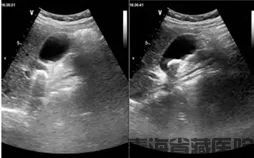

彩超是发现药物性胆囊结石的重要手段。在彩超图像上,它和普通胆囊结石表现相似,都能看到胆囊内的强回声团,后方伴有声影。不过,医生在诊断时会综合患者的用药史、症状等进行判断。比如患者近期有使用上述可疑药物,又出现右上腹疼痛、恶心等不适,检查发现胆囊结石,就会高度怀疑是药物性胆囊结石。